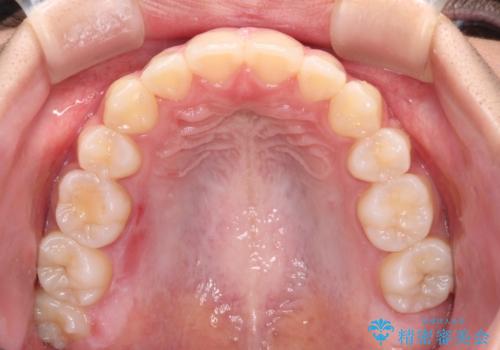

当初は八重歯やデコボコが一番気になっていましたが、抜歯矯正により口元の突出感が改善されるにつれ、口の閉じやすさを実感するようになってきました。

部活動で調整来院に来られないことがしばしばあり、期間は予定よりもかかりましたが、きれいに仕上げることができました。